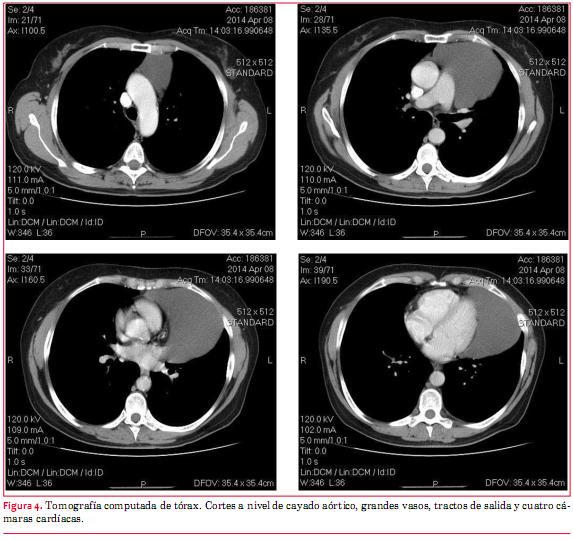

A continuación se realizó tomografía computada (TC) de tórax que mostró una voluminosa imagen quística de mediastino anterior, paracardíaca izquierda, con densidad similar a líquido en su interior, que se extendía desde un plano superior al cayado aórtico, hasta la proximidad del ángulo costo-frénico izquierdo. Su diámetro longitudinal era de 167 mm, transversal de 67 mm y anteroposterior de 93 mm. No había áreas de realce patológico con el contraste. No había adenomegalias hiliares ni mediastinales. No se observaba derrame pleural ni pericárdico. Se interpretó que podía corresponder a un quiste pericárdico (figura 4).

Hemos presentado el caso de una paciente asintomática con el hallazgo de un marcado incremento de la silueta cardíaca en una radiografía de tórax. El ecocardiograma mostró una extensa colección líquida paracardíaca y la tomografía de tórax mostró un voluminoso quiste de mediastino anterior, que se extendía desde encima del cayado aórtico hasta la proximidad del ángulo costo-frénico izquierdo.